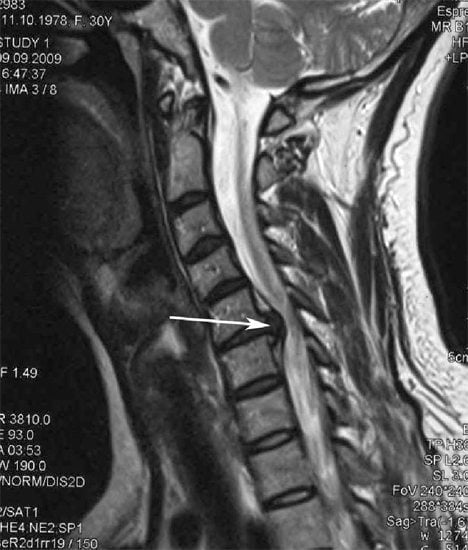

Для обнаружения причины вертеброгенного клинического проявления проводятся инструментальные исследования — МРТ, КТ, рентгенография, реоэнцефалография сосудов головного мозга. Их результаты позволяют оценить состояние позвоночной артерий, установить степень нарушения иннервации, обнаружить костные наросты в шейном отделе. Устранение головных болей проводится одновременно с терапией основной патологии — остеохондроза шейного отдела позвоночника.

По мере прогрессирования остеохондроза и разрушения большей части хрящевых тканей межпозвонковых дисков ситуация усугубляется. Для стабилизации позвонков, предупреждения их смещения начинают формироваться остеофиты, или костные разрастания. На рентгенографических изображениях они визуализируются в виде острых шипов, сдавливающих кровеносные сосуды.

Спровоцировать «отраженную» головную боль может ущемление нервных корешков позвонками в результате уплощения межпозвонковых дисков. В таких случаях дискомфортные ощущения не локализуются в шейном отделе, а иррадиируют в виски, затылок, плечи, предплечья. Если в позвоночнике уже сформировалась межпозвоночная грыжа (выпячивание межпозвонкового диска между телами позвонков), то болевой синдром усиливается при повороте или наклоне головы.